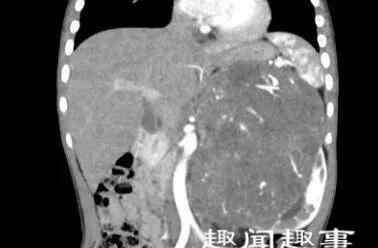

方方今年5岁,本该是长身体的年纪,但近3个月来,体重不升反而还轻了3公斤。在帮方方洗澡时,父母无意间发现方方左侧腰部鼓起了一个包。这可吓坏了父母,连忙带着小朋友到当地医院就诊,做彩超发现右肾居然长了一个14厘米的大肿瘤,跟方方的脑袋几乎一样大。

术中探查发现,方方的左肾和左侧肾上腺均已经受累,腹部大血管周围可见多发淋巴结肿大。但万幸的是肝、脾、胰腺等其他重要脏器没有受到侵犯。经过数小时的努力,多学科团队成功完成了左侧肾母细胞瘤根治性切除+腹膜后淋巴结清扫术。虽然经历了一场大手术,方方状态还是不错,平稳地回到了病房。